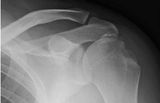

Мне кажется, что импрессионного перелома бугорка (повреждение Хилл-Сакса) здесь нет. При данном повреждении импрессия более выражена. Типичный перелом Хилл-Сакса выглядит примерно так.

Хотя, конечно, аксиальная проекция всё бы расставила по своим местам. На мой взгляд, второго перелома в области бугорка здесь нет.